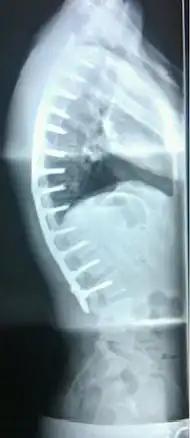

A post-operative X-ray of a 22-year-old male with Scheuermann's disease. After a 13-level spinal fusion to correct the excessive curvature, the person now presents a normal degree of kyphosis, with a minimal loss of flexibility.

In severe or extreme cases, patients may be treated through an extensive surgical procedure in an effort to prevent the disease from worsening or harming the body. The skeletal deformity caused by Scheuermann's disease can be corrected or partially corrected with surgical procedures, almost all of which include multi-level spinal fusion and hardware instrumentation, i.e., rods, pedicle screws, etc. It is important to realize the surgery aims to reduce pain, and not cosmetic defect. As always, surgical intervention should be used as a last resort once conservative treatment fails or the patient's health is in imminent danger as any surgical procedure is not without risk. However, the chances of complication are relatively low, and the surgeries are often successful.

There are two primary surgical techniques to correct kyphosis: posterior-only fusion and anterior/posterior fusion. While debate lingers over which surgical approach is optimal, several studies published since 2018 suggest treatment trends are favoring posterior-only fusion.[17][18][19]

The classic surgical procedure entails entering two titanium rods, each roughly 1.5 feet (0.46 m) long (depending on the size of the kyphosis) into the back on either side of the spine. Eight titanium screws and hardware are drilled through the bone to secure the rods onto either side of the spine. On the internal-facing side of the spine, ligaments (which can be too short, pulling the spine into its abnormal shape) must be surgically cut or released, not only stopping part of the cause of the kyphosis, but also allowing the titanium rods to pull the spine into a more natural position. The damaged discs between the troubled vertebrae (wedged vertebrae) are normally removed and replaced with bone grafting from the hip or other parts of the vertebrae, which once healed or "fused" will solidify. The titanium instrumentation holds everything in place during healing. The patient can expect to remain in hospital for a minimum of a week, and possibly longer. They may then be required to wear a brace for several months more to ensure the spine heals appropriately. The titanium instrumentation may stay in the body permanently, or be removed years later. Patients who have undergone such surgery may need physical therapy to manage pain and mobility. Recovery can be prolonged: typically patients are not allowed to lift anything above 5–10 pounds (2.3–4.5 kg) for 6 months to 1 year, and many are out of work for 3 to 6 months. However, once the fusion is solidified, most patients can return to their usual lifestyle within 1–2 years.